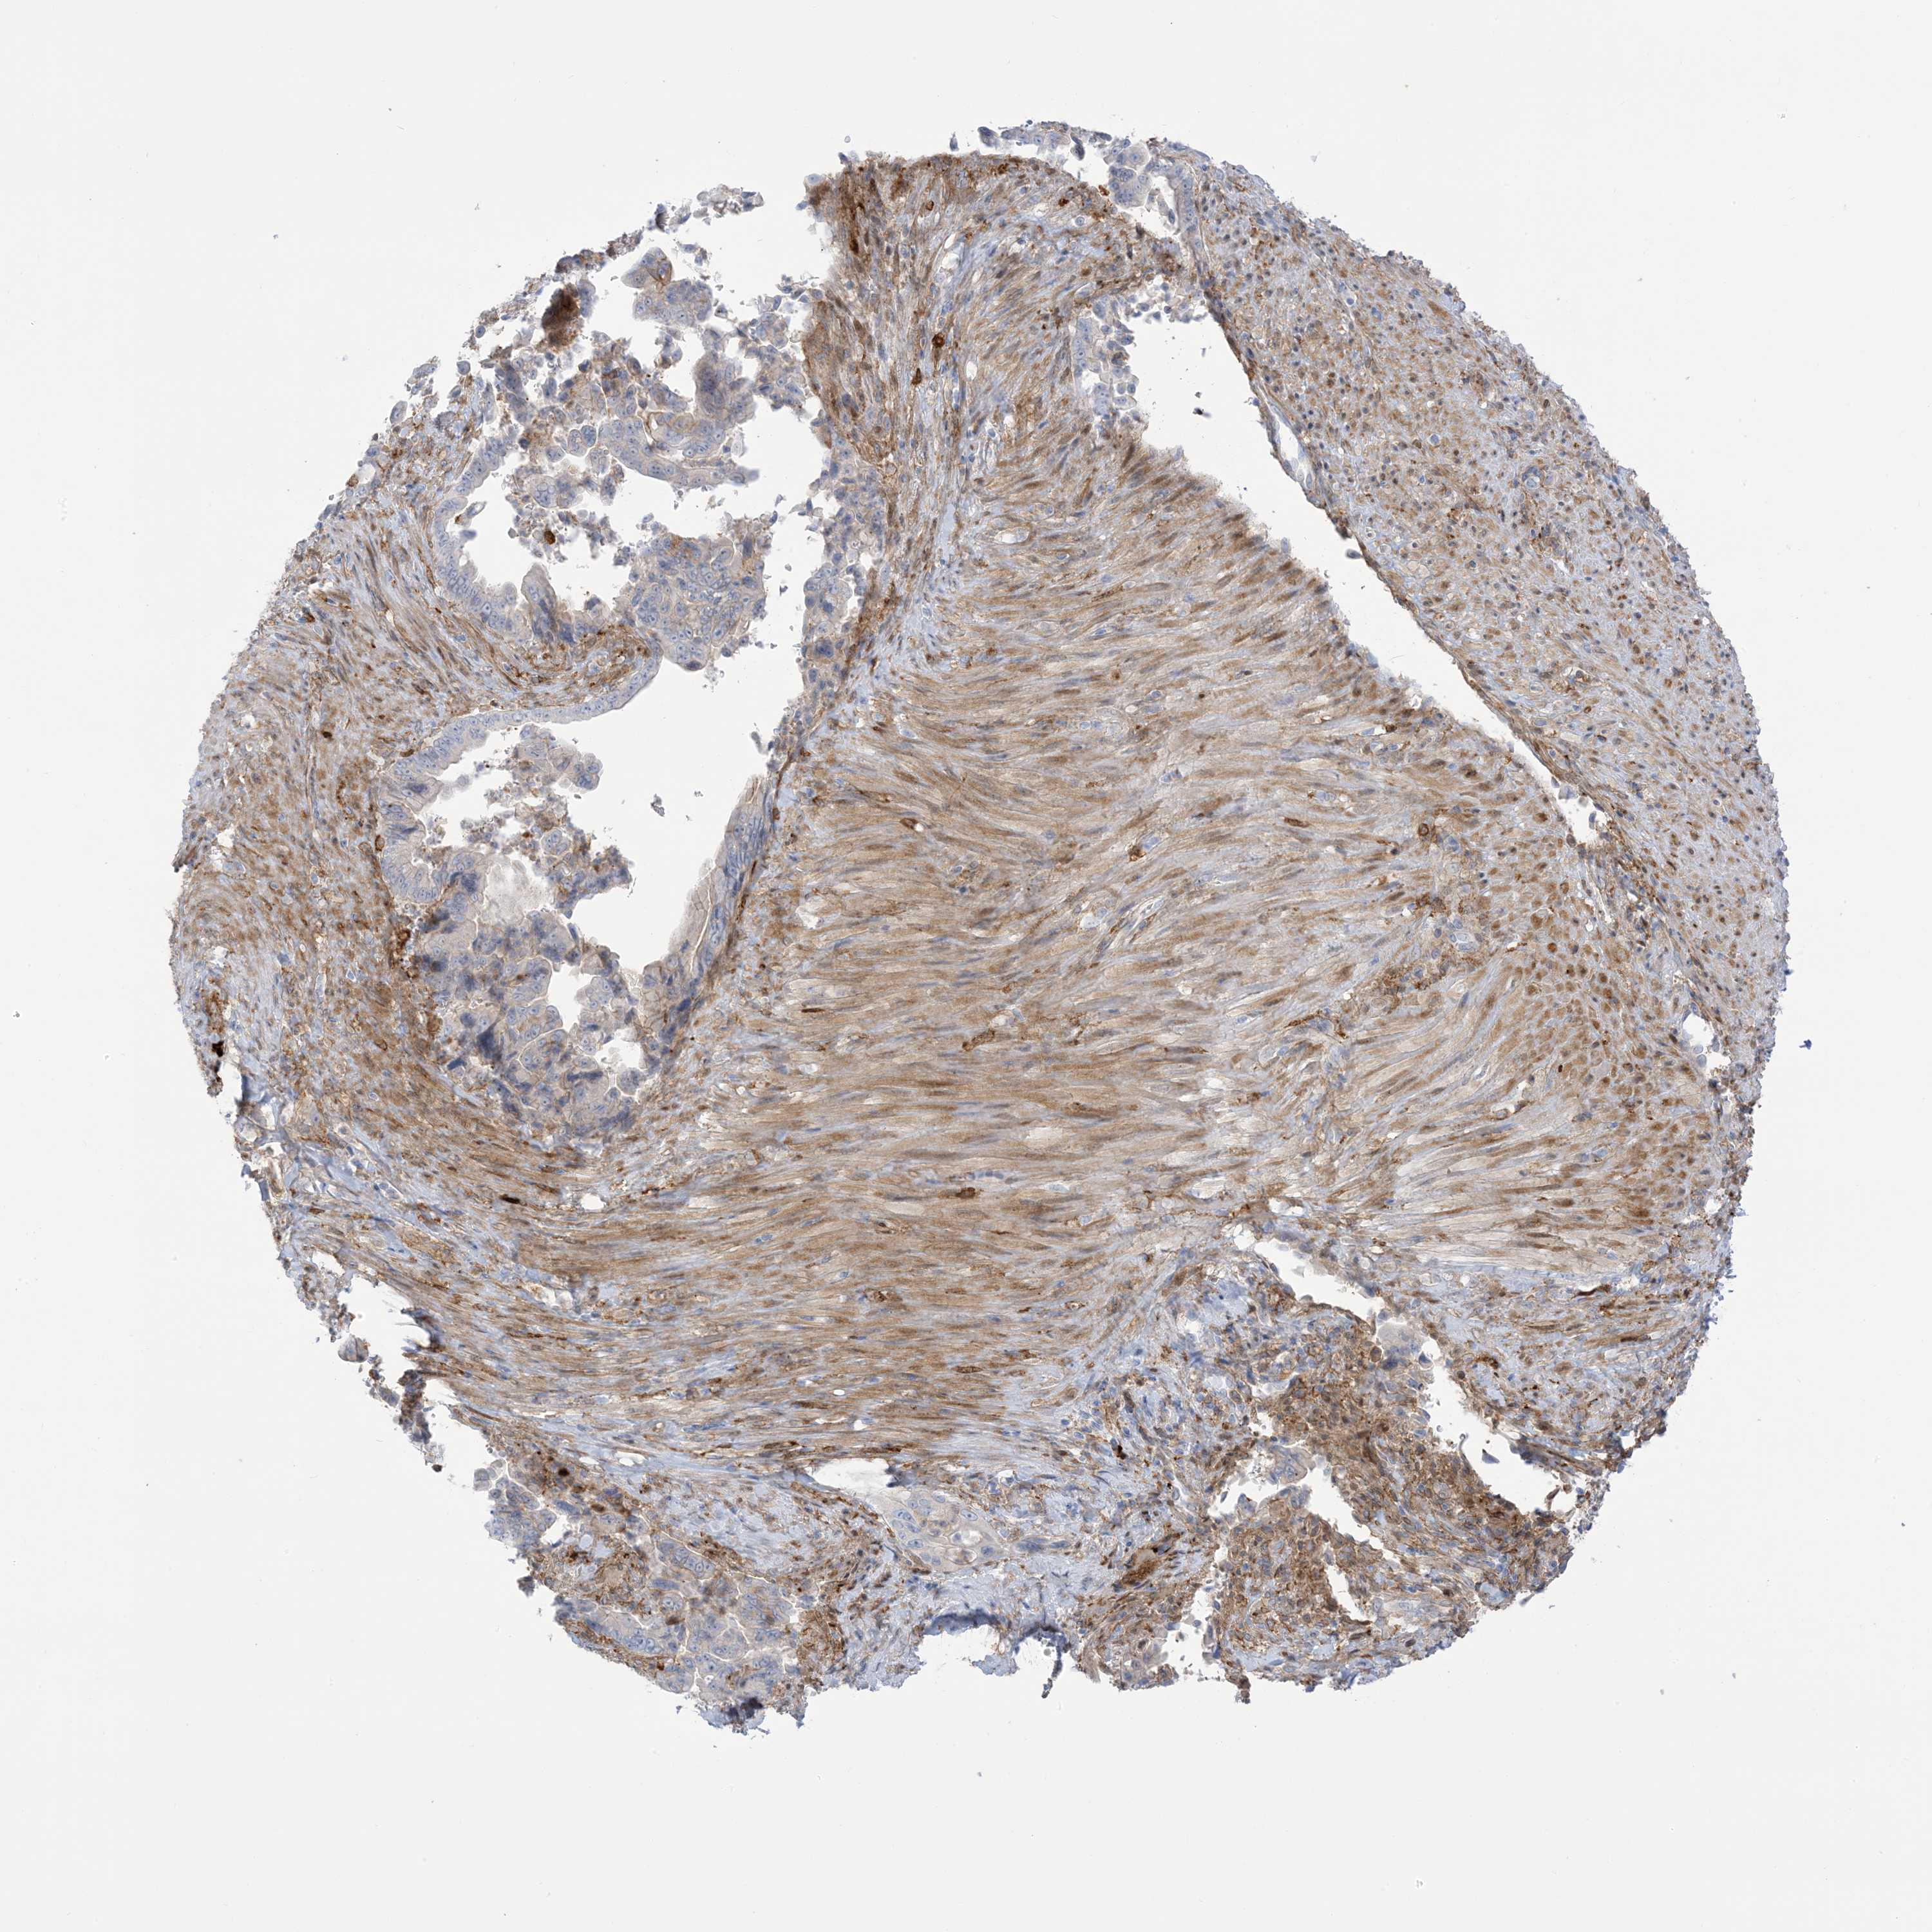

PANCREATIC CANCER - Protein expressioni

A mouse-over function shows sample information and annotation data. Click on an image to view it in a full screen mode. Samples can be filtered based on level of antibody staining by selecting one or several of the following categories: high, medium, low and not detected. The assay and annotation is described here.

Note that samples used for immunohistochemistry by the Human Protein Atlas do not correspond to samples in the TCGA dataset.

Antibody stainingi

Antibody staining in the annotated cell types in the current human tissue is reported as not detected, low, medium, or high, based on conventional immunohistochemistry profiling in selected tissues. This score is based on the combination of the staining intensity and fraction of stained cells.

Each image is clickable and will lead to virtual microscopy that enables deeper exploration of all samples and also displays staining intensity scores, fraction scores and subcellular localization as well as patient and tissue information for each sample.

Antibody HPA032024

Antibody HPA032025

Staining

High

Medium

Low

Not detected

Intensity

Strong

Moderate

Weak

Negative

Quantity

>75%

75%-25%

<25%

None

Location

Nuclear

Cytoplasmic/membranous

Cytoplasmic/membranous,nuclear

Adenocarcinoma, NOS